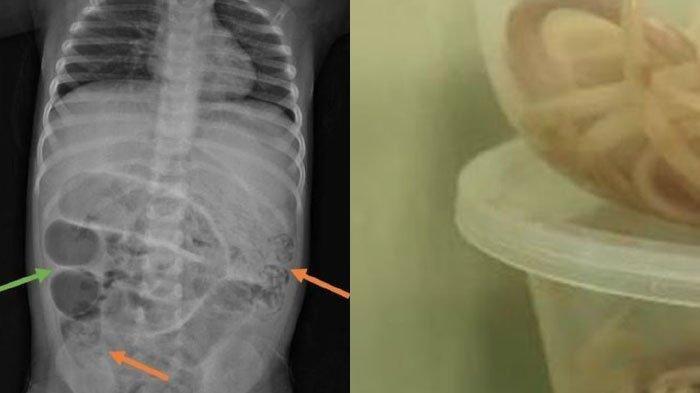

Heboh Ada Cacing Hidup di Tubuh Balita, Hingga Buat Perut Membesar Seminggu Tak BAB Akhirnya Dibedah

Heboh ada cacing hidup di tubuh balita laki-laki berusia 3 tahun hingga akhirnya dibedah.

SURYAMALANG.COM - Heboh ada cacing hidup di tubuh balita laki-laki berusia 3 tahun hingga akhirnya dibedah.

Akibat ada cacing yang hidup di tubuhnya, perut si balita pun membesar sampai tidah bisa BAB selama seminggu.

Bahkan, anak tersebut juga mengalami sakit perut, kesulitan bernapas, dan muntah.

Dokter di rumah sakit menduga hal itu terjadi karena ada sumbatan pada ususnya sehingga tidak berfungsi maksimal.

"Kemudian diperiksa CT scan, memang menggambarkan suatu kondisi yang disebut ileus obstruktif, yaitu buntunya saluran pencernaan akibat sesuatu," ucapnya.

Saat dirawat di dalam ruangan, pasien tersebut muntah mengeluarkan cacing.

Para dokter tersebut menyimpulkan bahwa ada proses darurat yang harus dilakukan operasi pada anak tersebut.

"Akhirnya diputuskan untuk operasi karena sudah mengganggu fungsi pencernaan dan pernapasan," ucap dia.